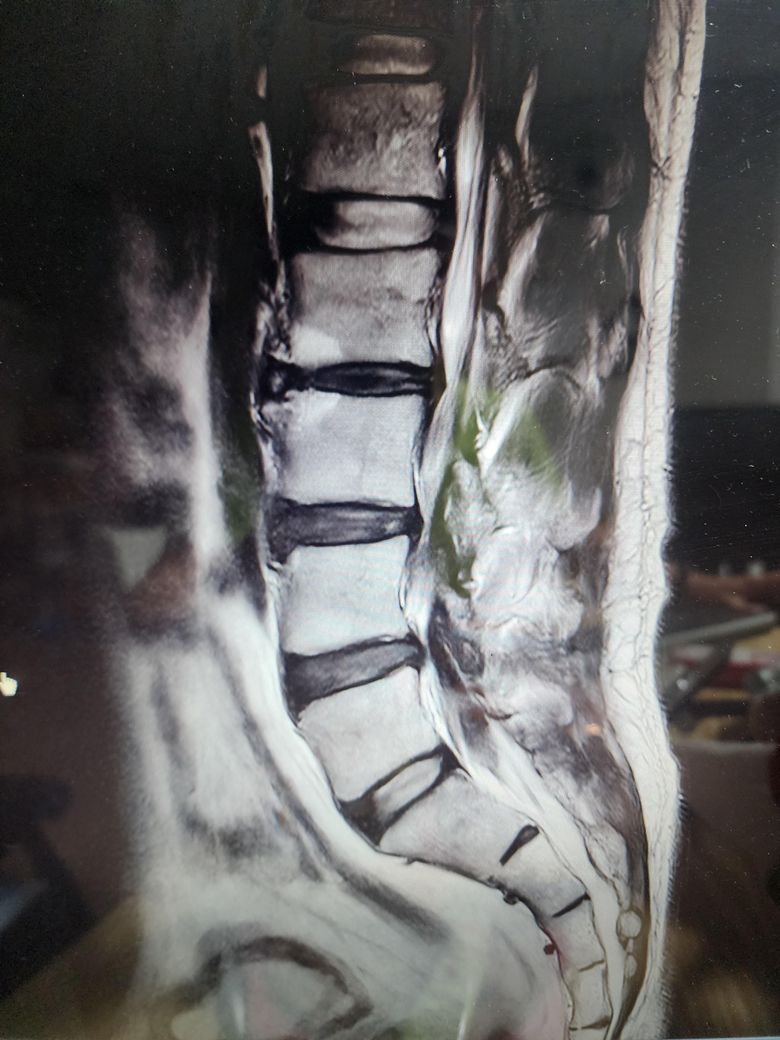

• 2번 째 사진

보여주신 MRI 상에는 척추관 협착증은 전혀 보이지 않습니다.

아래 첫번째 그림에 보시는것과 같이 B에서 보이듯이 검정색 신경뿌리 주변의 하얀색 뇌척수액이 공간 없이 비좁아지는 정도는 되어야 척추관 협착증이라고 이야기할 수 있을텐데 보여주신 MRI 에는 이런 모습은 없습니다.

정확하게는 제가 두번째로 올린 작성자분의 허리 MRI 사진중에서 빨간색 동그라미로 표시한 부분의 단면을 확인해야 더 정확한 설명이 가능하긴 하겠습니다.

추간판 공간이 줄어들어있고, 디스크 증상처럼 돌출이나 퇴행적 변화가 관찰되는 것으로 생각되는데요, 결국에 수술적 치료를 하더라도 보존적인 치료법을 먼저 시행하여 경과를 살펴보고 차도가 없는 경우 수술을 고려하는 것이 많기 때문에 우선 보존적 치료가 가능한 경우라면 수술은 조금 더 나중에 고려를 해보시는 것도 좋겠습니다. 수술을 고려중이신 경우에는 가능한 여러 전문의들의 의견을 들어보시는 것도 좋은 방법이 될 수 있겠습니다.